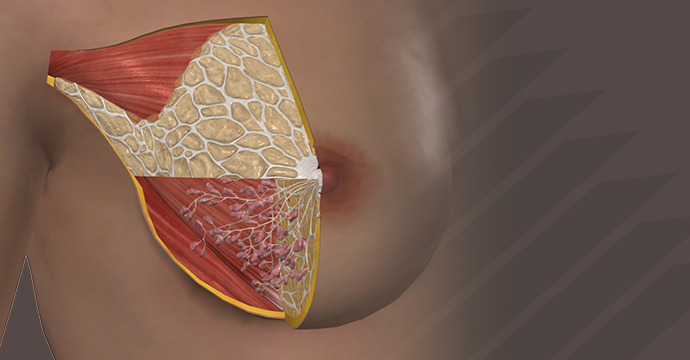

Take your understanding of human anatomy to the next level. Our comprehensive resources combine detailed information and stunning illustrations!

Enhance your studies for a truly dynamic learning experience. Explore interactive anatomy models from Complete Anatomy. Start mastering anatomy today with our free anatomy flashcards designed for quick review on the go.